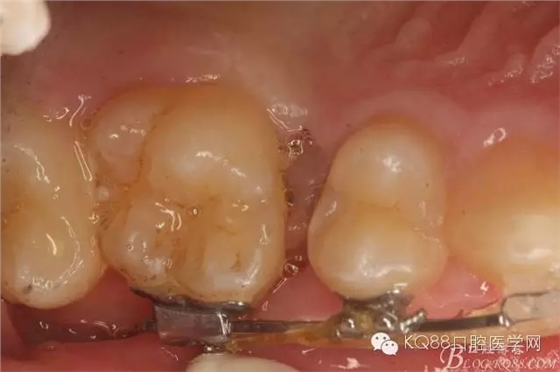

圖1.術(shù)前患者的口內(nèi)照片:16與14之間有約2mm間隙,矯治器已經(jīng)安裝到位。